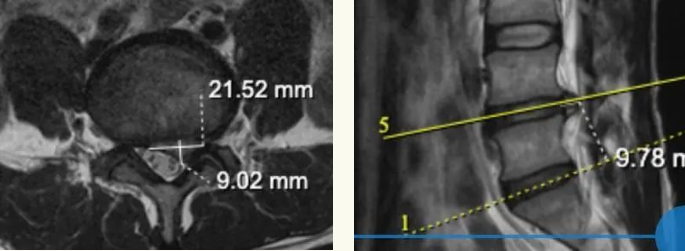

术前及术后核磁共振影像对比发现,术后突出的间盘(髓核)完全去除效果良好,完全保留关节突关节,预计3月后,完整保留的纤维环和后纵韧带将完全回缩。

术前影像

术后影像